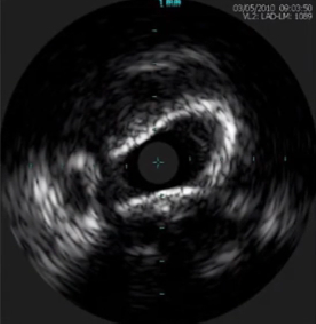

4、钙化斑块影像

声影前缘出现在斑块厚度管腔侧50%以内为表浅钙化。

声影前缘出现在斑块厚度外弹力膜侧50%以内为深层钙化。

表浅钙化

深层钙化

全层钙化

根据钙化斑块沿管腔分布弧度分级:

I级: ≤90°

I级: 91° —180°

Ⅲ级:181° —270°

Ⅳ级: >271°

钙化斑块影像